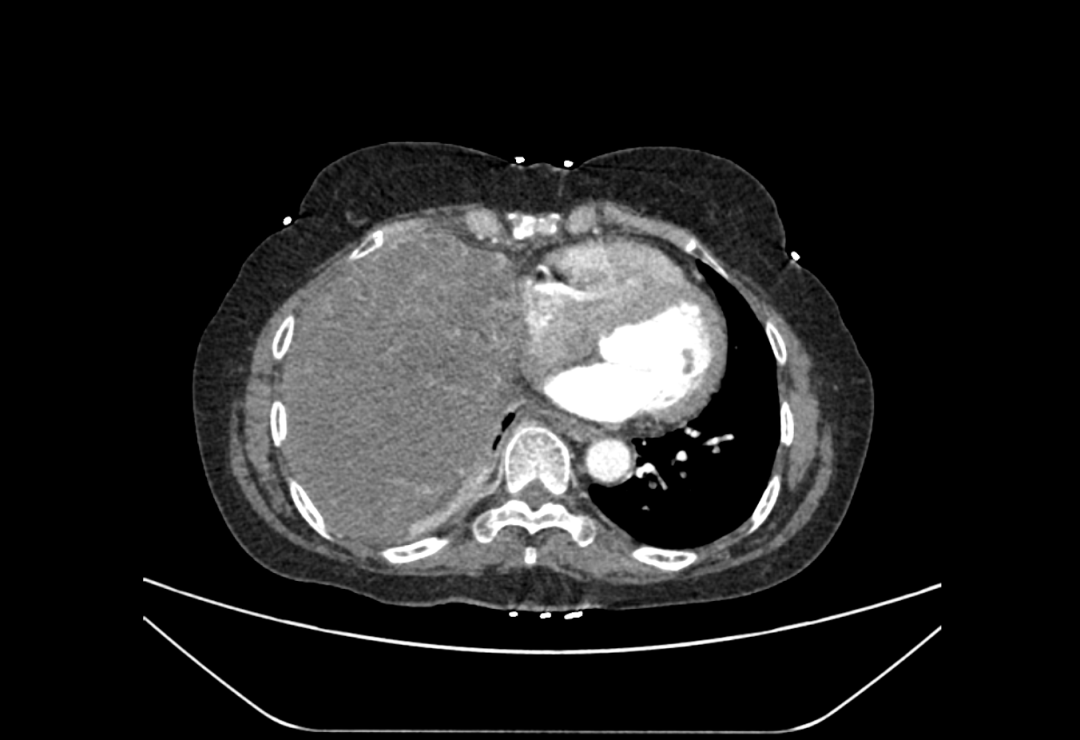

CT检查显示肿瘤占据患者整个右侧胸腔

66岁的王女士因“胸痛伴胸闷憋气”来到青大附院平度院区急诊科就诊,随后被收治于呼吸与危重症医学科进一步治疗。经全面检查,治疗团队震惊地发现她的右侧胸腔内长有一个罕见的大肿瘤,已严重压迫心肺组织,如不及时干预,后果不堪设想。面对患者的严重病情,呼吸与危重症医学科立即组织多学科会诊,经综合评估,手术切除肿瘤成为解除患者病痛、挽救生命的唯一途径。

术中,刘玉洪主任团队在麻醉科及手术室医护团队的协助下,凭借丰富的手术经验,精准游离患者肿瘤与周围重要组织粘连,成功将大小约25cm×15cm的右侧胸腔大肿瘤完整切除。术后,患者身体恢复顺利,未出现神经系统及心肺相关并发症,现已康复出院。